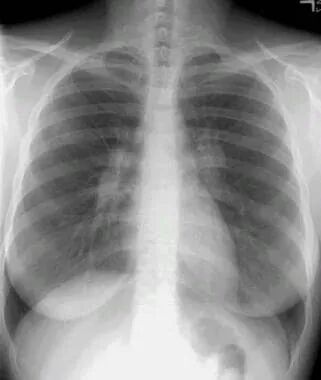

图1 双肺门淋巴结肿大